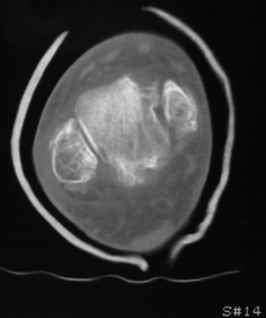

Остеопороз (продолжение 3) - данные КТ

Юрий Алексеевич Булахтин 07 Ноябрь 2009, 16:27

|

Уважаемые коллеги!

Продолжая тему представляю данные КТ нашей пациентки.

Вопросы к сообществу - в сообщении №2.

Юрий Алексеевич Булахтин